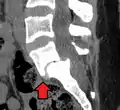

MRI of L5-S1 anterolisthesis

Anterolisthesis L5/S1

Magnetic Resonance Imaging (MRI)

Magnetic resonance imaging is the preferred advanced imaging technique for evaluation of spondylolisthesis.[30] Preference is due to effectiveness, lack of radiation exposure, and ability to evaluate for soft tissue abnormalities and spinal canal involvement.[30][31] MRI is limited in its ability to evaluate fractures in great detail, compared to other advanced imaging modalities.[32]